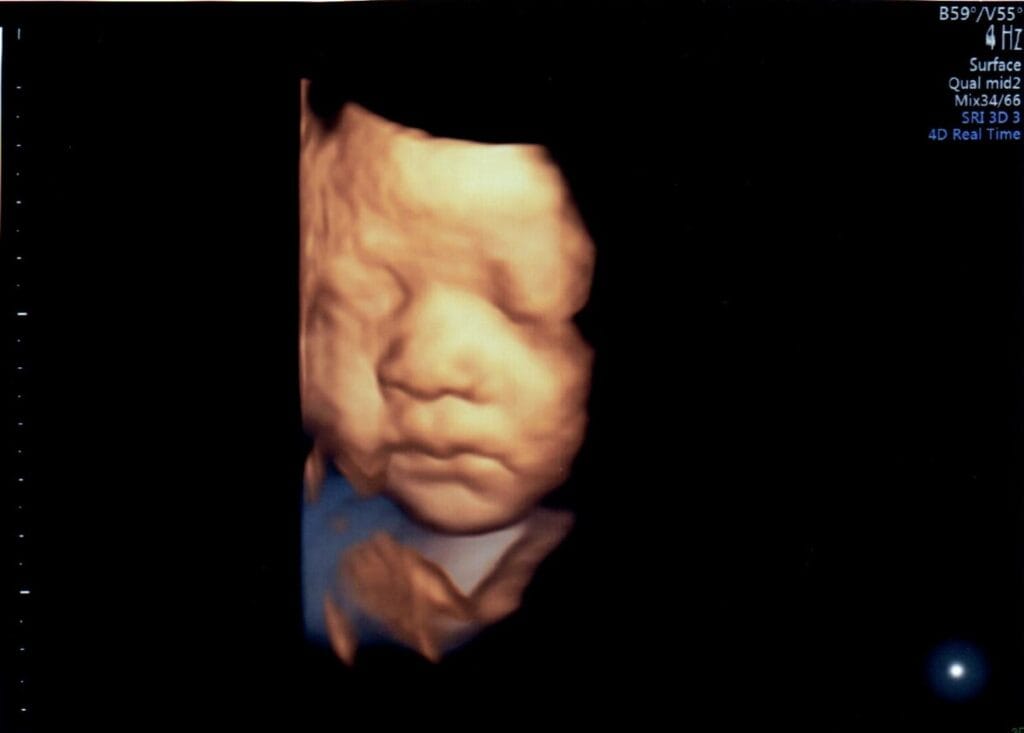

妊婦健診時に3D・4D超音波を行っています

妊婦健診の超音波測定で、赤ちゃんの様子がわかる3D・4D超音波を行っています。

胎位により、3D・4D画像がうつりにくい場合がありますので、週数時期については、技師にお任せください。

ご理解の程、よろしくお願いいたします。

胎位により、映り方には個人差があります。